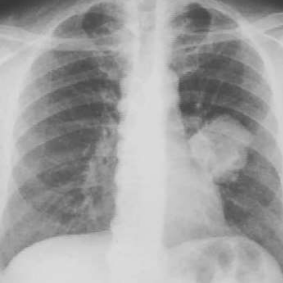

<p>¿Qué estudio es?</p>

¿Qué estudio es?

Radiografía simple